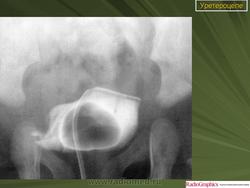

Уретероцеле.

Приложения:

Уретероцеле